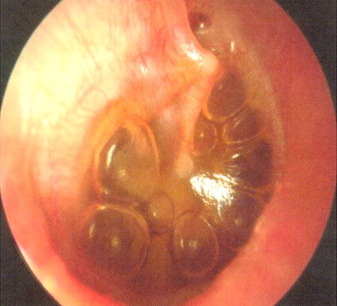

Otitis media with effusion

Otoscopy of otitis media with effusion, showing air fluid levels or bubbles, with normal tympanic membrane landmarks

From the personal collection of Dr Armengol